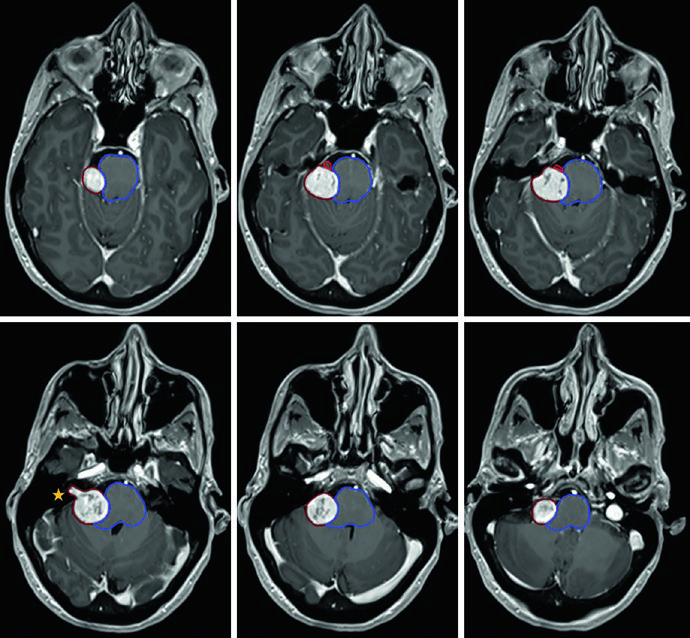

Um ponto prático crucial: a avaliação da TC é essencial para decidir se alterações periosteais e ósseas devem ser incluídas no GTV. No exemplo do meningioma do seio cavernoso (Figura 29.7), o tumor foi delineado com RM de planejamento, recebeu margem de 2 mm para o PTV e foi tratado a 52,2 Gy em 29 frações. As linhas de isodose mostram conformação apertada ao redor do tronco encefálico, quiasma, nervos cranianos adjacentes, artéria carótida e cóclea.

Meningiomas volumosos selares e suprasselares com ressecção incompleta — como na Figura 29.8 — podem requerer expansão de PTV de 3 mm por causa da doença residual extensa. A relação íntima com os globos e o tronco encefálico exige planejamento dosimétrico cuidadoso, frequentemente com IMRT ou VMAT para conformar a dose e proteger essas estruturas.